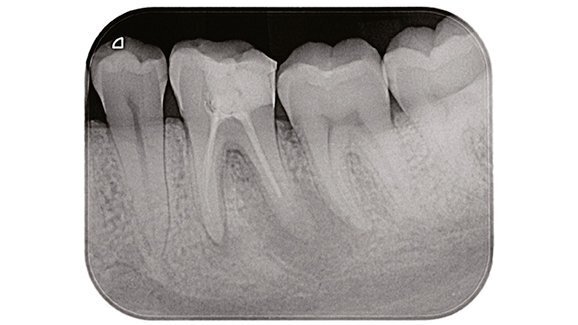

Il fallimento endodontico è un’evenienza che può capitare se rimangono batteri all’interno del sistema canalare come conseguenza di una insufficiente disinfezione, di un’inadeguata otturazione oppure quando viene meno il sigillo coronale1 (Fig. 1a). L’errore potrebbe essere risolto con successo grazie ad un ritrattamento per via ortograda2 oppure, se questo non è possibile, da un ritrattamento per via chirurgica.

Le tecniche non chirurgiche richiedono la completa rimozione del vecchio materiale da otturazione presente nello spazio endodontico al fine di ottenere una sagomatura, disinfezione e otturazione tridimensionale del sistema canalare più profonda e completa: condizioni indispensabili per ottenere il successo3 (Figg. 1b, 1c).